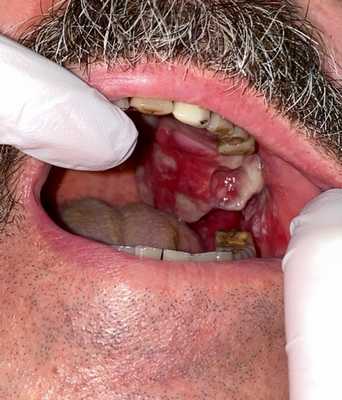

— Осмотр опытного специалиста, врача-онколога; На фото можно увидеть, как выглядит саркома мягких тканей:

— Рентгенологическое исследование. Позволяет визуализировать тень опухоли, деформацию прилежащих к опухоли фасциальных перемычек, выявить изменения в костях;

— УЗИ опухолей мягких тканей. Это метод диагностики как первичного очага, так и поражения региональных зон. Позволяет определить границы опухоли, связь с окружающими органами, структуру опухоли;

Рисунок №1. Саркома мягких тканей бедра. УЗ-картина в серошкальном и сосудистом режимах визуализации